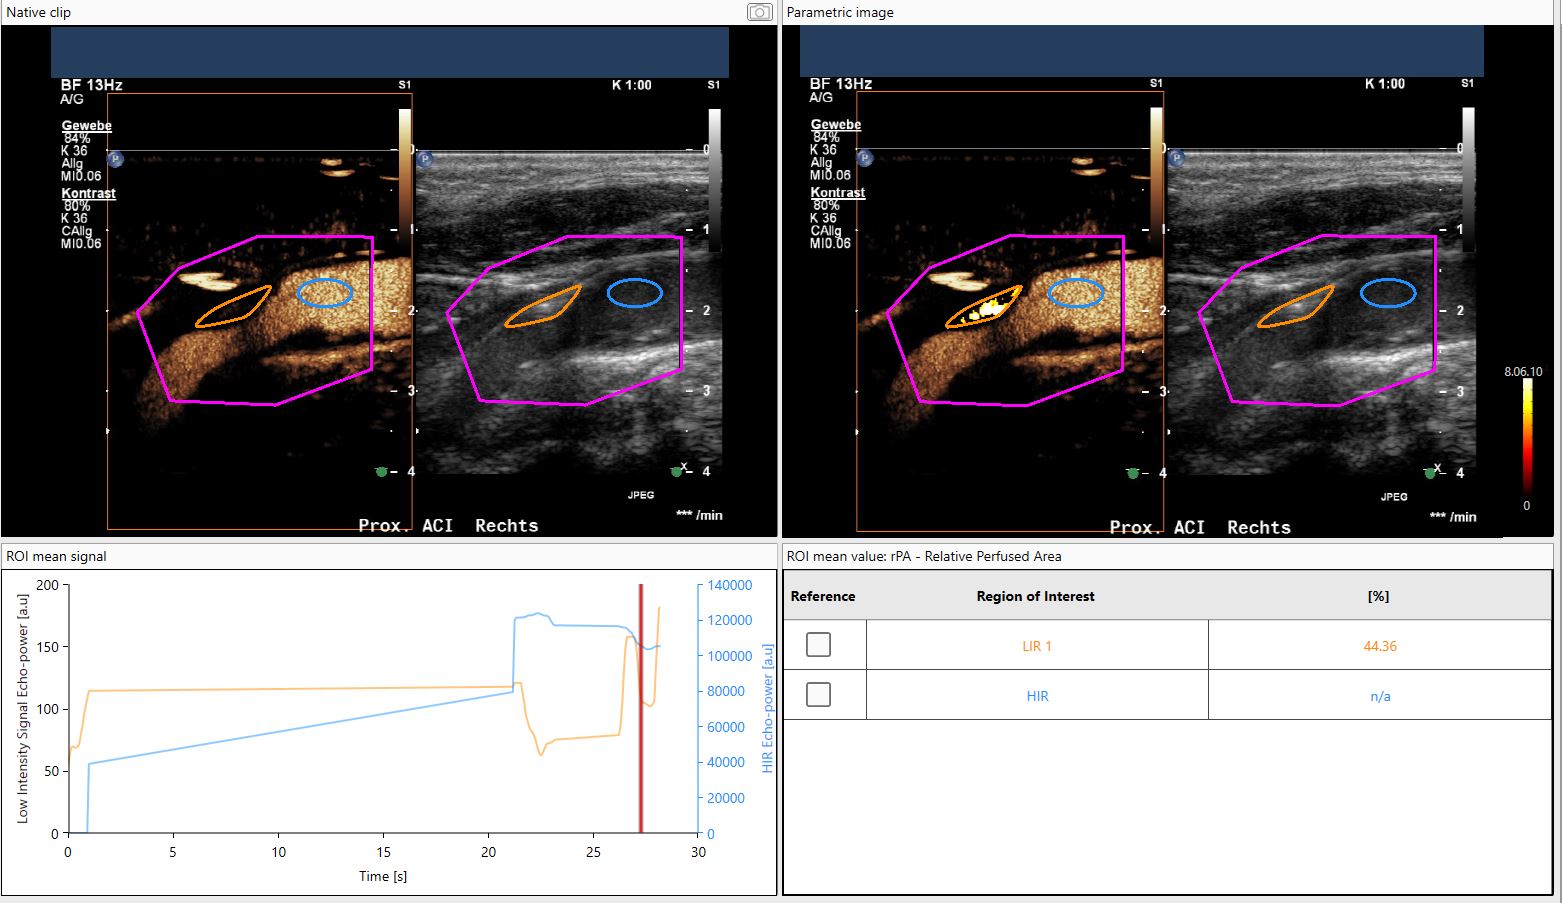

Low-Intensity Signal

• To detect vascularization and determine vascularized areas in low-intensity signal areas.

• Specific vascularization parameters: ROI area, perfused area, relative perfused area, mean opacification.